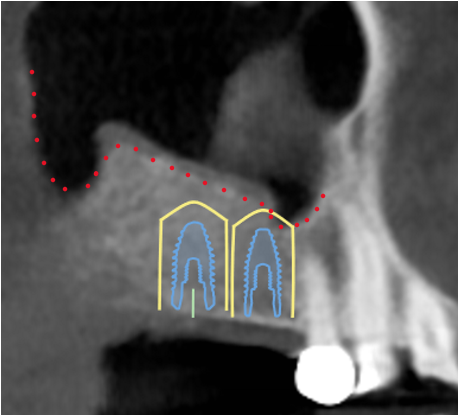

The case below demonstrates one of many exceptional results that have been obtained utilizing the sinus lift technique.

Preoperatively, a CBCT is taken to identify that inadequate bone is present underneath the sinus cavity (outlined in red dotted line). Placement of a 10mm length implant (minimum length recommended for molar sized teeth) would lead to an extensive amount of the implant sticking into the “hollow” space of the sinus cavity. This creates long term problems with the sinus as well as problems with implant healing and longevity.